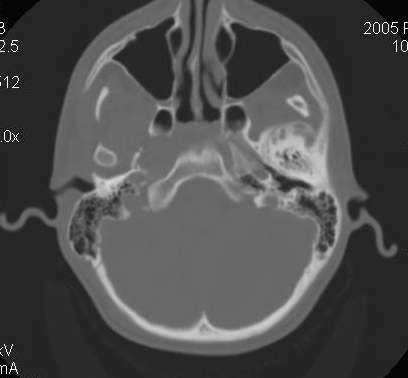

Пациент В., 13 лет. Диагноз: Костный анкилоз левого височно-нижнечелюстного сустава (ВНЧС), левосторонняя микрогения. Болеет с 2-х летнего возраста. Возможная причина развития анкилоза – воспалительный процесс (в первые 1,5 года жизни часто болел простудными заболеваниями, травму родители отрицают). В 3 и 5 лет проводилась редрессация – безуспешно. Прилагаются: ортопантомограмма, кадры СКТ с 3Д реконструкцией. Вопросы: определение тактики лечения – вид и сроки реконструктивно-пластической операции (этапов операции), а именно – неоартропластики и устранения микрогении, медикаментозная терапия в до- и послеоперационный период, ортодонтическое лечение.